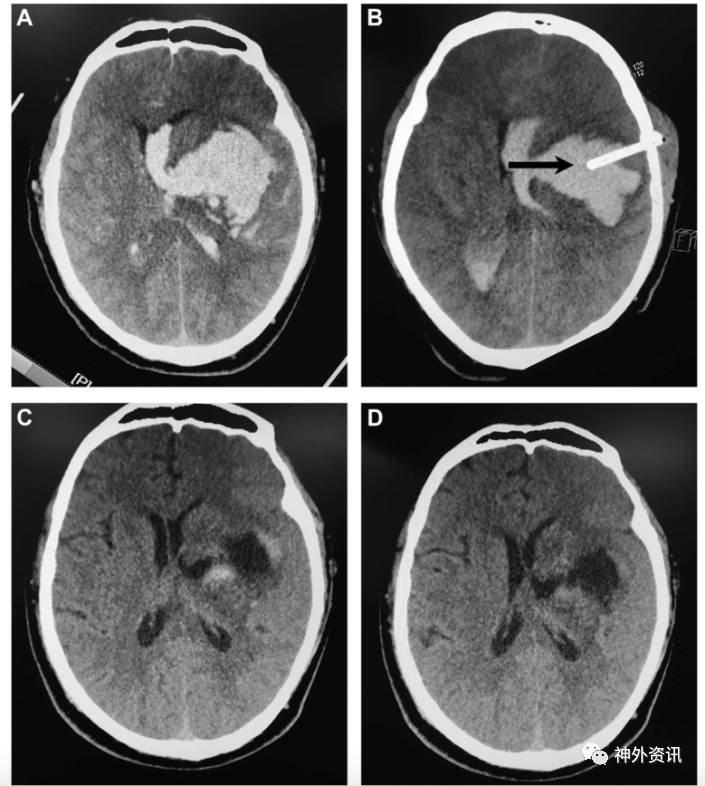

图1. 64岁男性患者,左侧基底节出血,血肿量约73ml。A.术前CT平扫;B.术后即刻CT平扫,见单根引流管在血肿腔内(黑箭头);C.术后第7天CT扫描,示血肿大部分已清除;D.术后2周CT扫描,示残余血肿完全吸收。